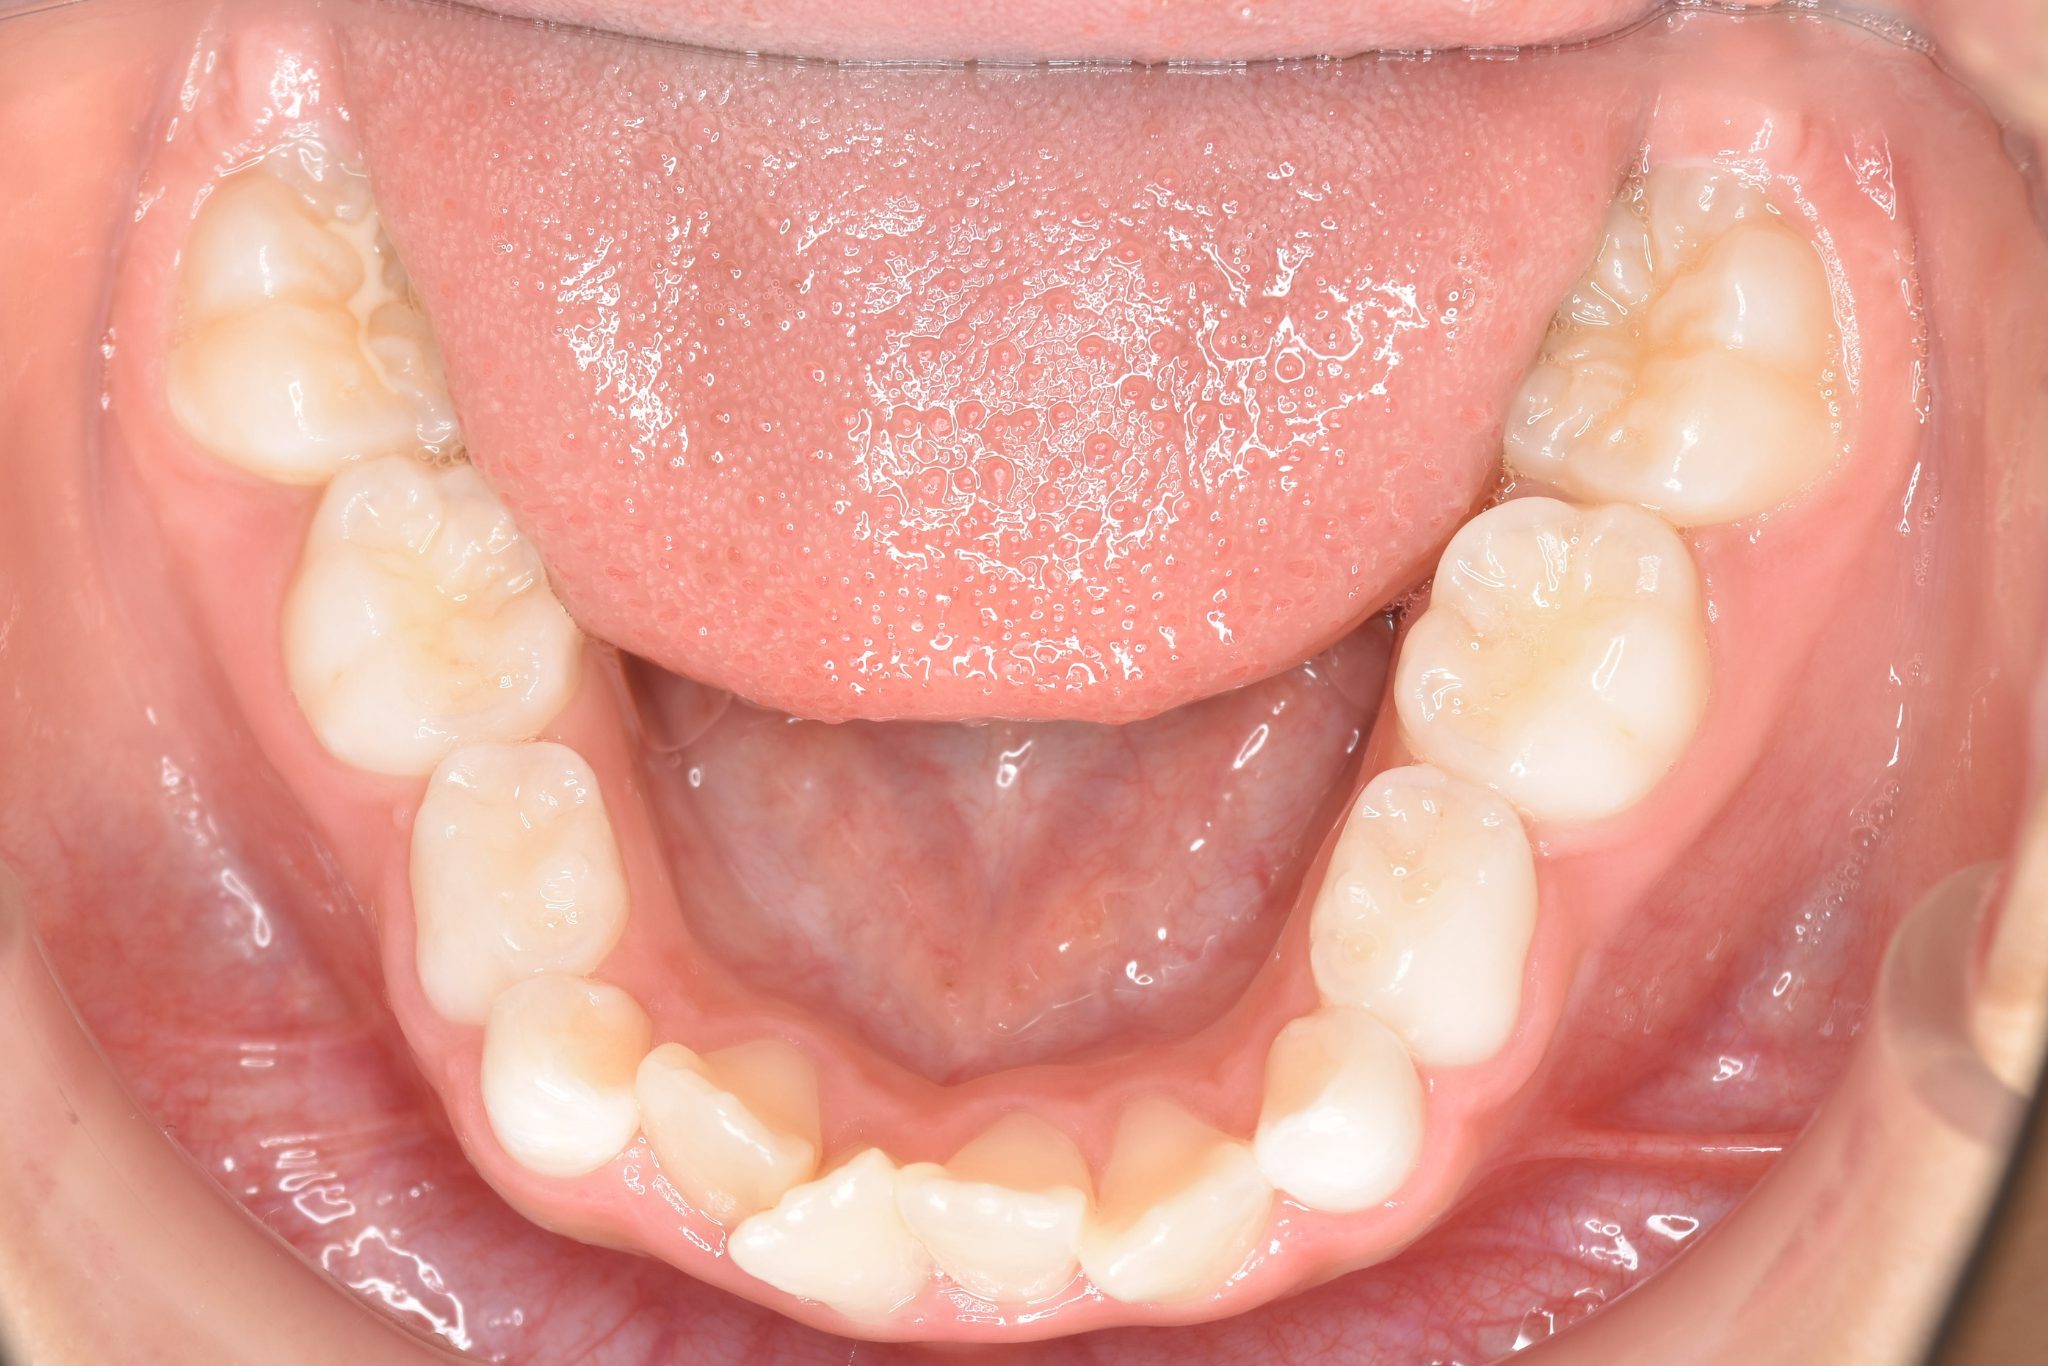

全顎ワイヤー矯正 症例_610 Case

ビフォー

| 主訴 | 前歯の歯並び|歯ぎしり |

| 施術内容 | 小児矯正1期治療 |

| 治癒期間 | 2年4か月間 |

| 費用 | 711,700円(税込) |

| リスク・副作用 | 違和感、不快感、痛み |